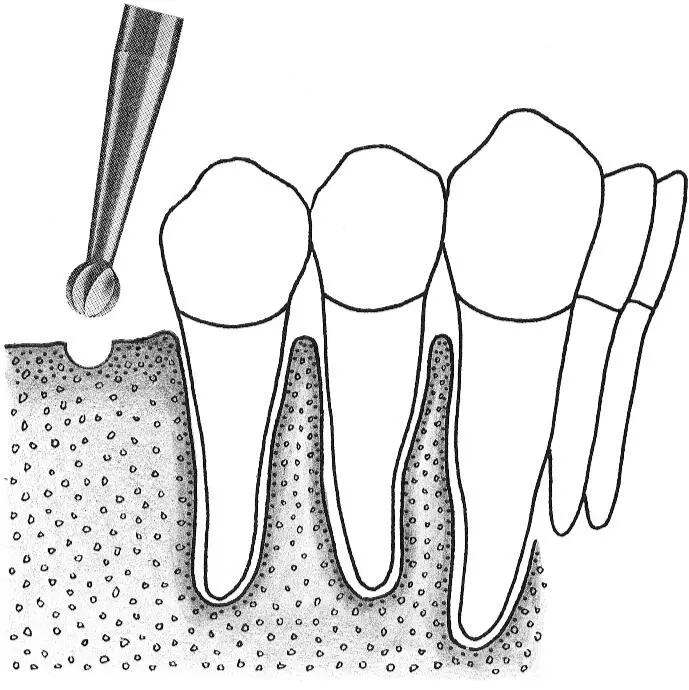

Fig 1-1Smoothing the alveolar crest following flap elevation.

Fig 1-1a Once the implant surgical site has been exposed, a large round bur is used to smooth and level the crest of the alveolar ridge.

Fig 1-1b All sharp edges and irregularities are removed by running the round bur across the alveolar ridge.

Fig 1-1c In this cross section, the irregular, narrow crest is smoothed to produce a flat, wide ridge, which is favorable for implant site preparation.